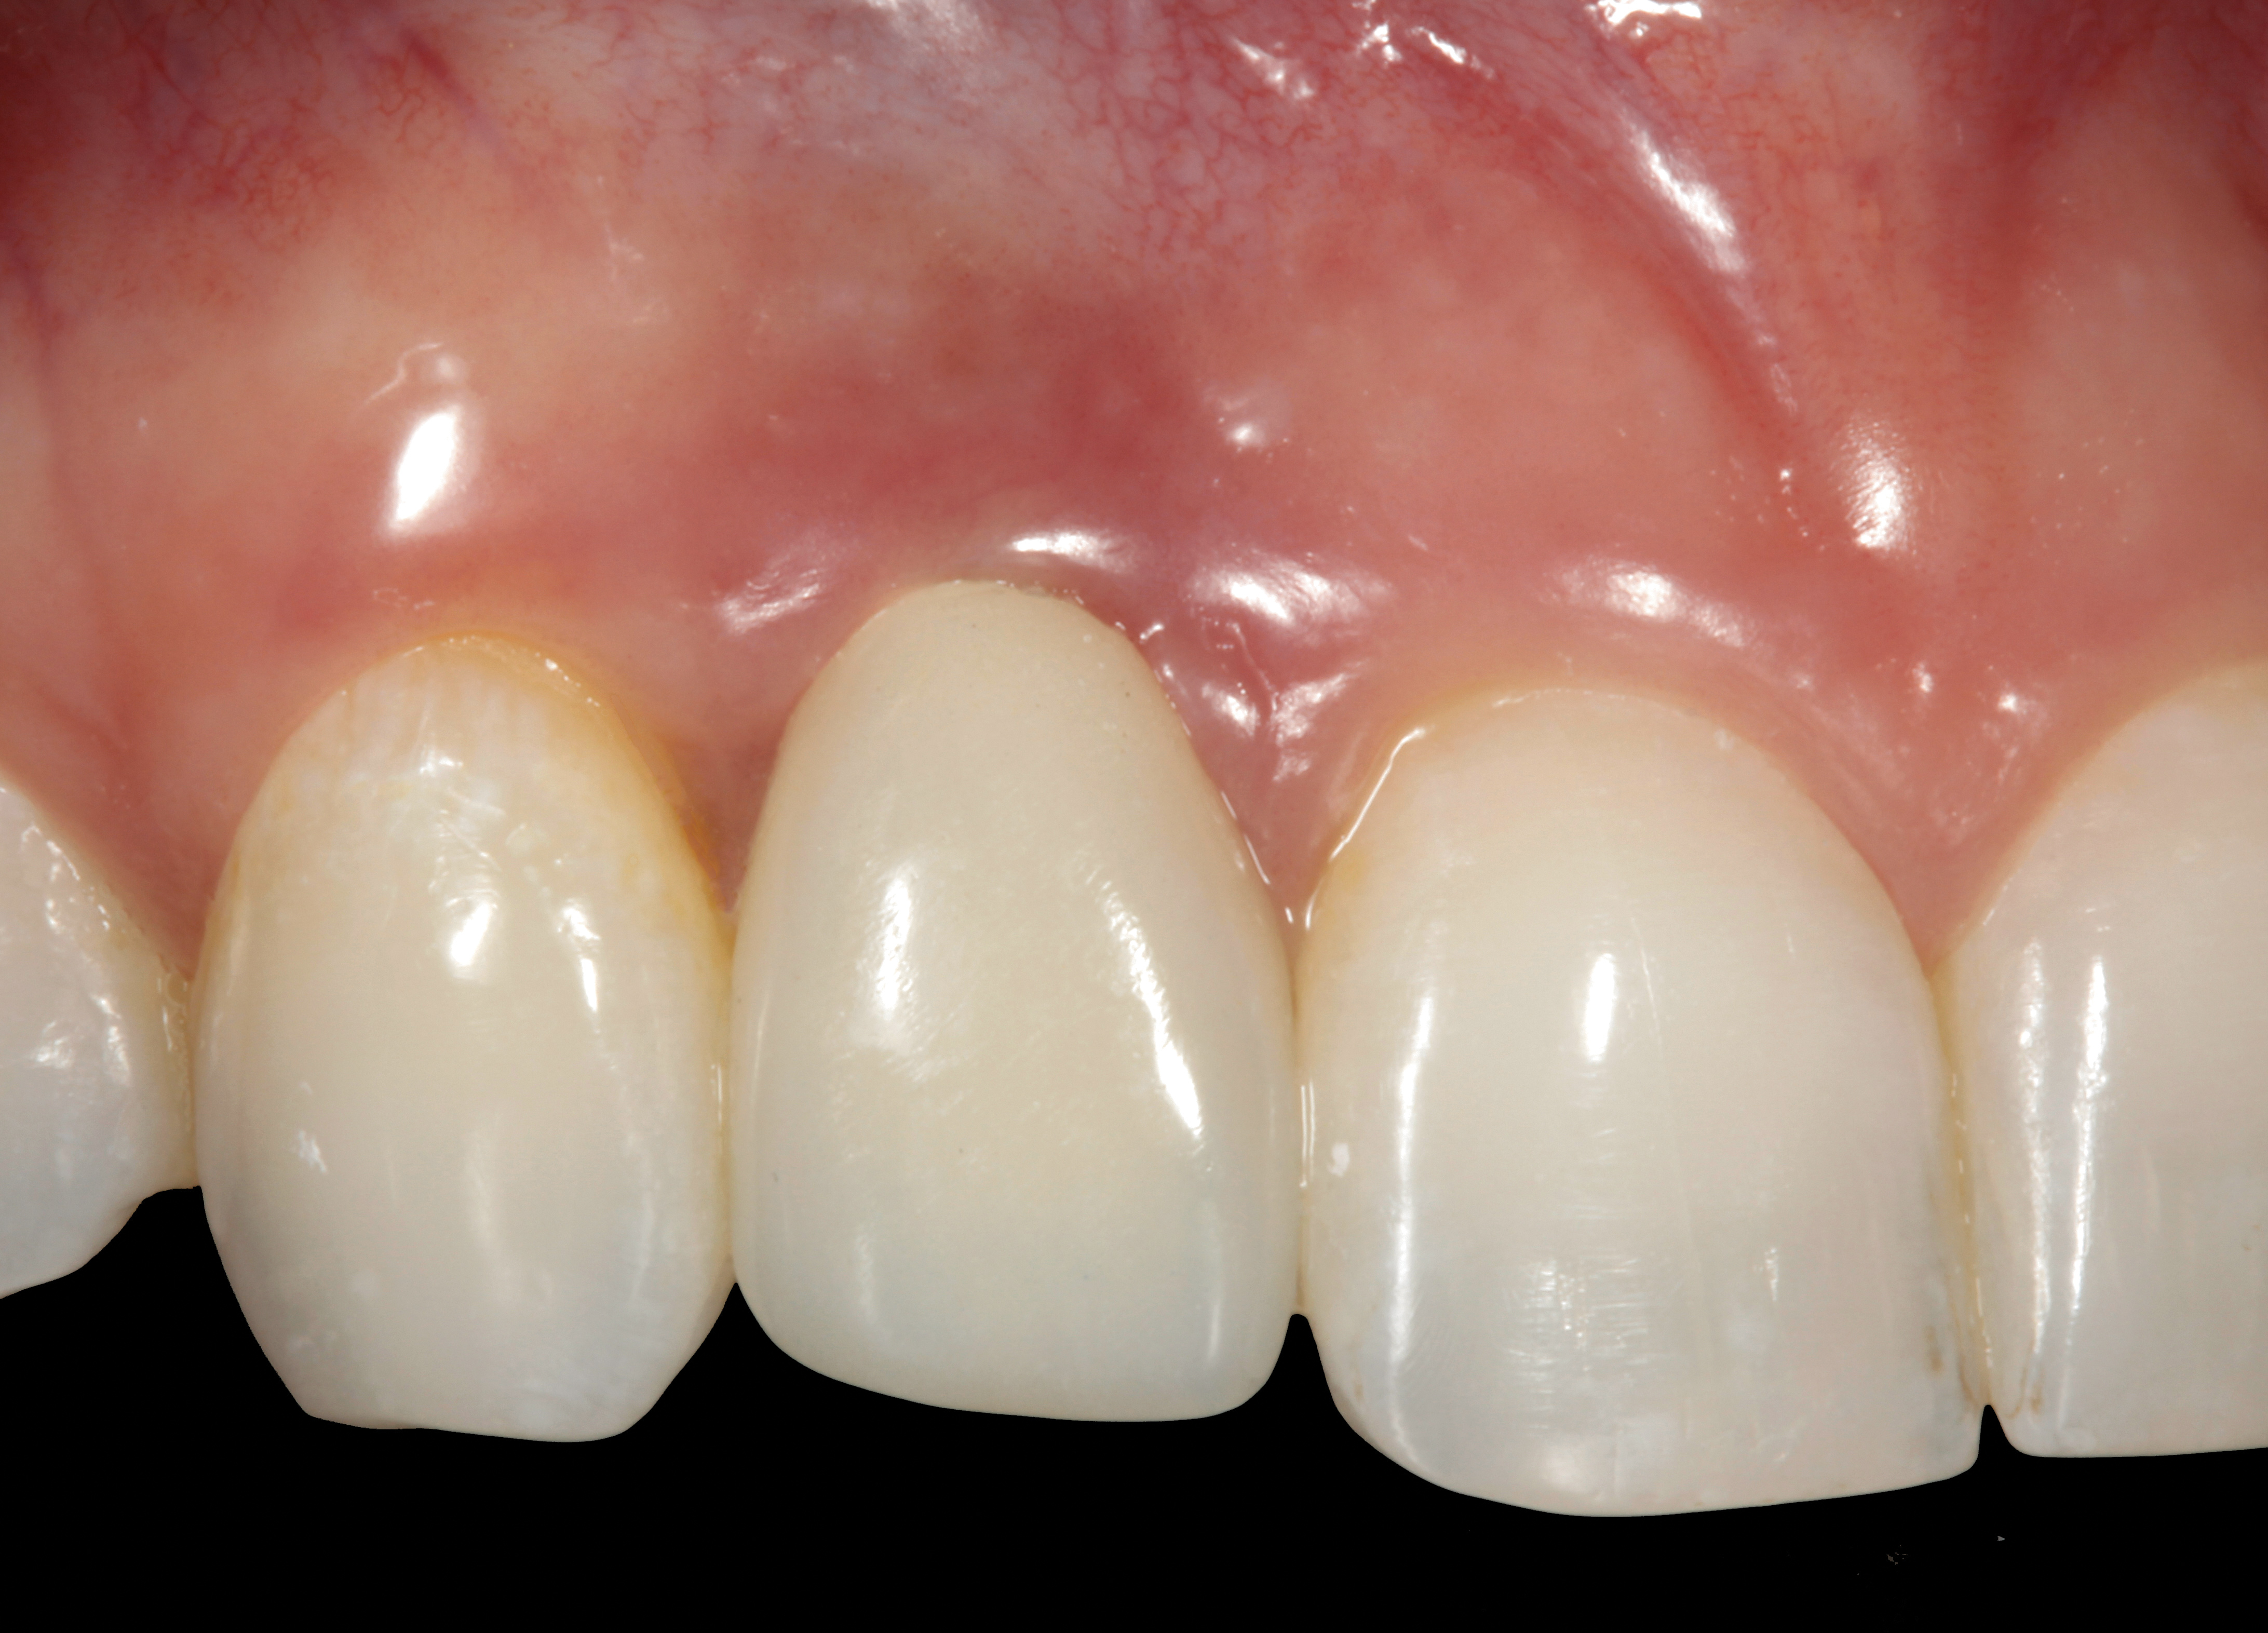

Fig 1. Midfacial recession can affect the esthetics of a smile and lead to an unsatisfactory outcome.

Figure 1

Fig 2. The cause for midfacial recession is excessive labial implant placement. Secondary to poor placement is overcontouring of the implant abutment.

Figure 2

Problem: The implant is placed too facial with significant recession on the midfacial aspect of the abutment and/or crown; the implant is healthy and the patient has a high smile line with an intermediate to thick periodontal phenotype (Figure 1 and Figure 2).17-19